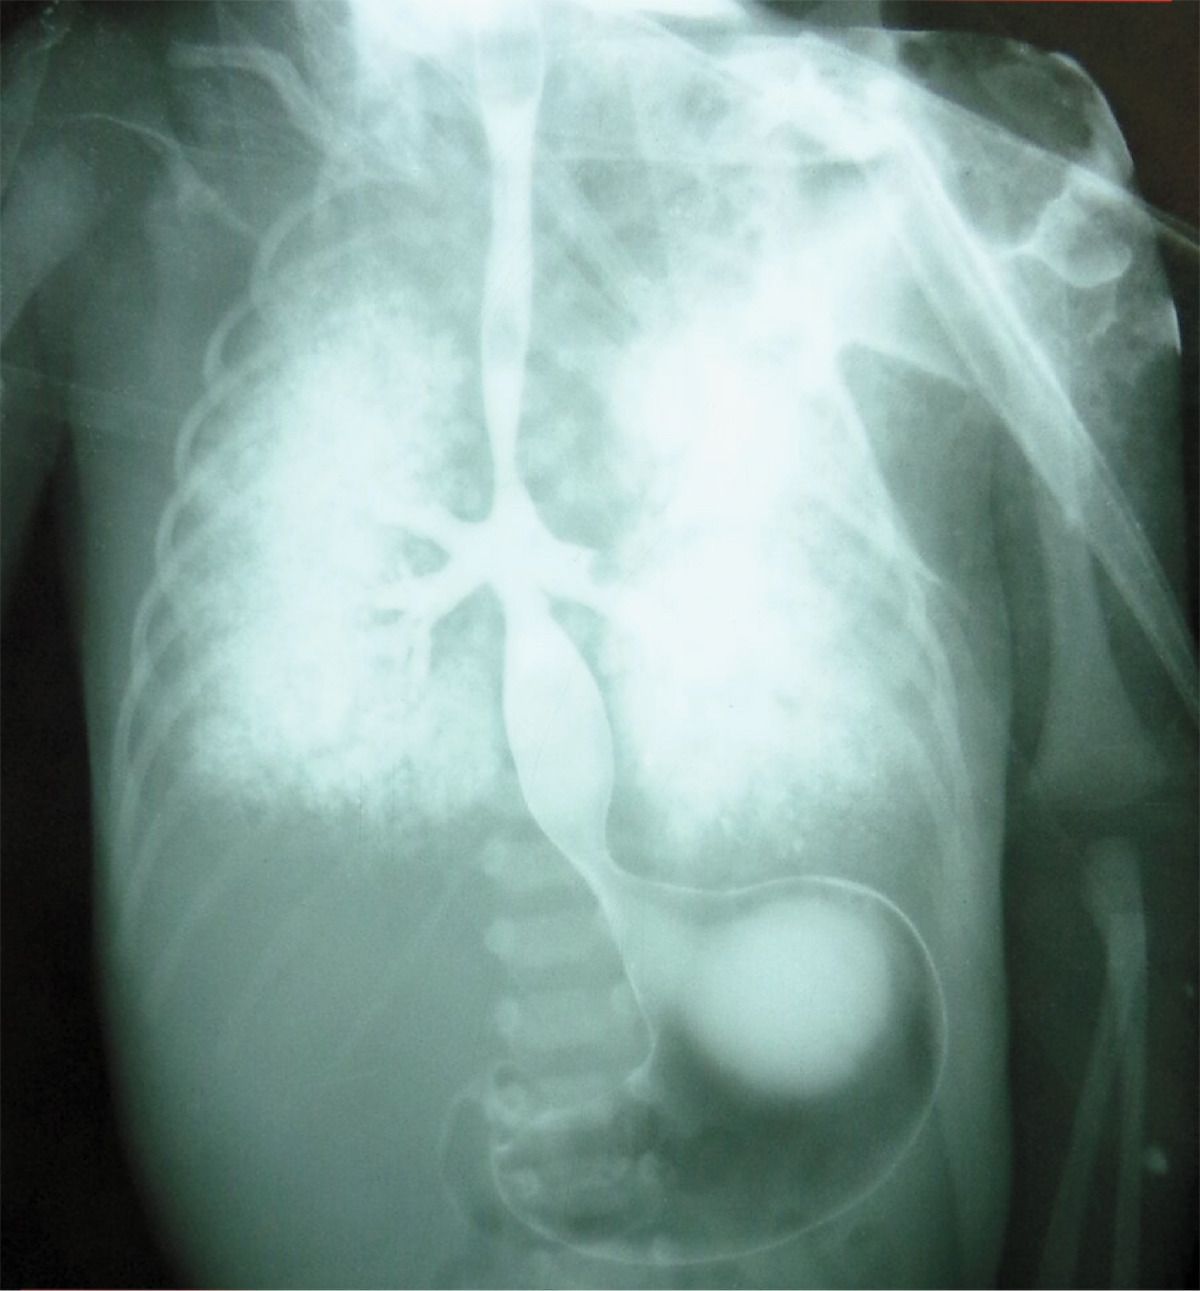

Cyanosis and respiratory distress developed in a neonate after delivery at 32 weeks of gestation. His mother had not received regular antenatal care. Endotracheal intubation and tracheostomy were attempted without success, and bag-valve–mask ventilation was performed, but the boy died from respiratory failure 4 hours after delivery. An esophagram obtained post mortem, after the administration of barium, suggested tracheal agenesis and bronchoesophageal fistula. An autopsy confirmed absence of the trachea, with fusion of the main bronchi and bronchoesophageal fistula, findings consistent with a diagnosis of type II tracheal agenesis, defined in accordance with the Floyd classification system. Additional findings included dysmorphic facial features, a double superior vena cava, an ostium secundum atrial septal defect, and a horseshoe kidney. Postnatal karyotyping revealed trisomy 18. Diagnostic advances, including those enabling assessment of the fetus on sonography and magnetic resonance imaging, have facilitated the establishment of this diagnosis prenatally.